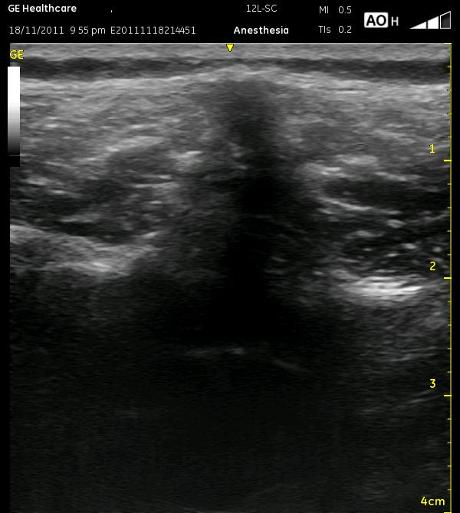

The following ultrasound picture shows a potential misunderstanding which can lead to confusion while scanning and with needle placement. Can you identify the shadow of the Spinous Process, Erector Spinous Muscles and the Transverse Processes? Have a look before you look further at the next ultrasound picture.

OK, it was a trick question. The white lines immediately lateral to the Spinous Process shadow are actually the Lamina (or maybe Facets). I hope you recognized the other two structures though. This is an easy early misconception in learning this block because we are so focused on locating the Transverse Processes, and we see bones sticking out lateral to the spinous process and think we’re there. The Transverse Processes extend laterally from the anterior aspect of the lamina above the pedicle. The transverse processes are out more lateral and deep to the lamina.